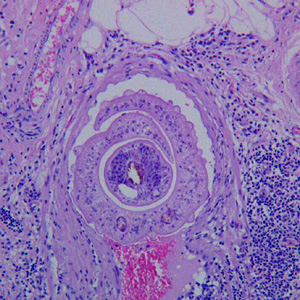

A 35-year-old woman went to her health care provider with complaints of abdominal pain, cramps and diarrhea. She told her doctor that she had recently returned from a business trip to Mexico. Stool was collected in 10% formalin and polyvinyl alcohol (PVA) for routine ova-and-parasite (O&P) examination.